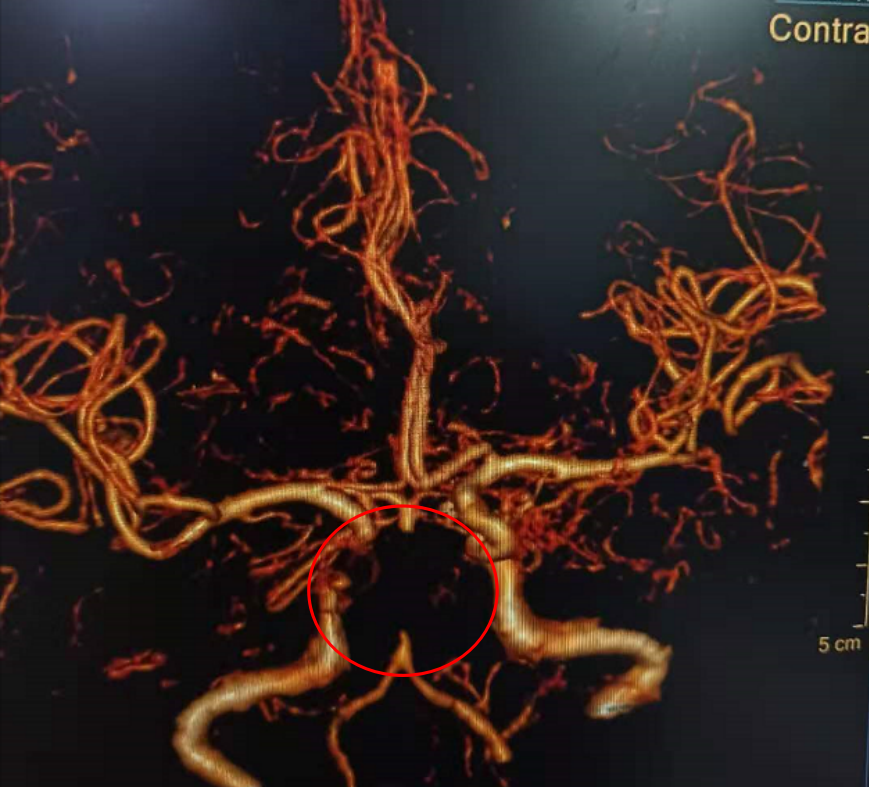

入院颅脑CT未见明显异常;头颈CTA提示基底动脉闭塞;

DSA示:基底动脉下段闭塞。